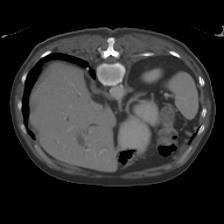

In clinical practice, well-aligned multi-modal images, such as Magnetic Resonance (MR) and Computed Tomography (CT), together can provide complementary information for image-guided therapies. Multi-modal image registration is essential for the accurate alignment of these multi-modal images. However, it remains a very challenging task due to complicated and unknown spatial correspondence between different modalities. In this paper, we propose a novel translation-based unsupervised deformable image registration approach to convert the multi-modal registration problem to a mono-modal one. Specifically, our approach incorporates a discriminator-free translation network to facilitate the training of the registration network and a patchwise contrastive loss to encourage the translation network to preserve object shapes. Furthermore, we propose to replace an adversarial loss, that is widely used in previous multi-modal image registration methods, with a pixel loss in order to integrate the output of translation into the target modality. This leads to an unsupervised method requiring no ground-truth deformation or pairs of aligned images for training. We evaluate four variants of our approach on the public Learn2Reg 2021 datasets \cite{hering2021learn2reg}. The experimental results demonstrate that the proposed architecture achieves state-of-the-art performance. Our code is available at https://github.com/heyblackC/DFMIR.

图像配准是图像处理研究领域中的一个典型问题和技术难点,其目的在于比较或融合针对同一对象在不同条件下获取的图像,例如图像会来自不同的采集设备,取自不同的时间,不同的拍摄视角等等,有时也需要用到针对不同对象的图像配准问题。具体地说,对于一组图像数据集中的两幅图像,通过寻找一种空间变换把一幅图像映射到另一幅图像,使得两图中对应于空间同一位置的点一一对应起来,从而达到信息融合的目的。 该技术在计算机视觉、医学图像处理以及材料力学等领域都具有广泛的应用。根据具体应用的不同,有的侧重于通过变换结果融合两幅图像,有的侧重于研究变换本身以获得对象的一些力学属性。